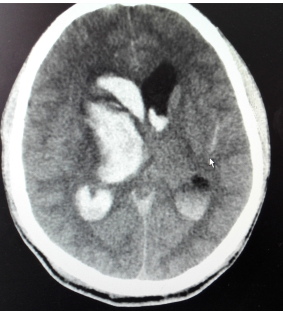

男性,50岁,右侧基底节区脑出血破入脑室、颅内高压,行颅内血肿微创清除术,有效清除了颅内积血,降低颅内压,患者恢复良好。

手术前